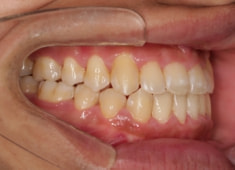

解説:残存している左上乳犬歯Cを抜歯し、そのスペースに左上3番を誘導しました。Cと犬歯ではスペースが足りないので、前歯をアドバンスさせ、反対咬合を同時に解消しております。

治療前

治療後(2年1ヶ月後)

大臼歯は整直されております。

歯根のパラレリングは良好です。

特に左側の咬合時の顎関節の位置に改善が認められます。